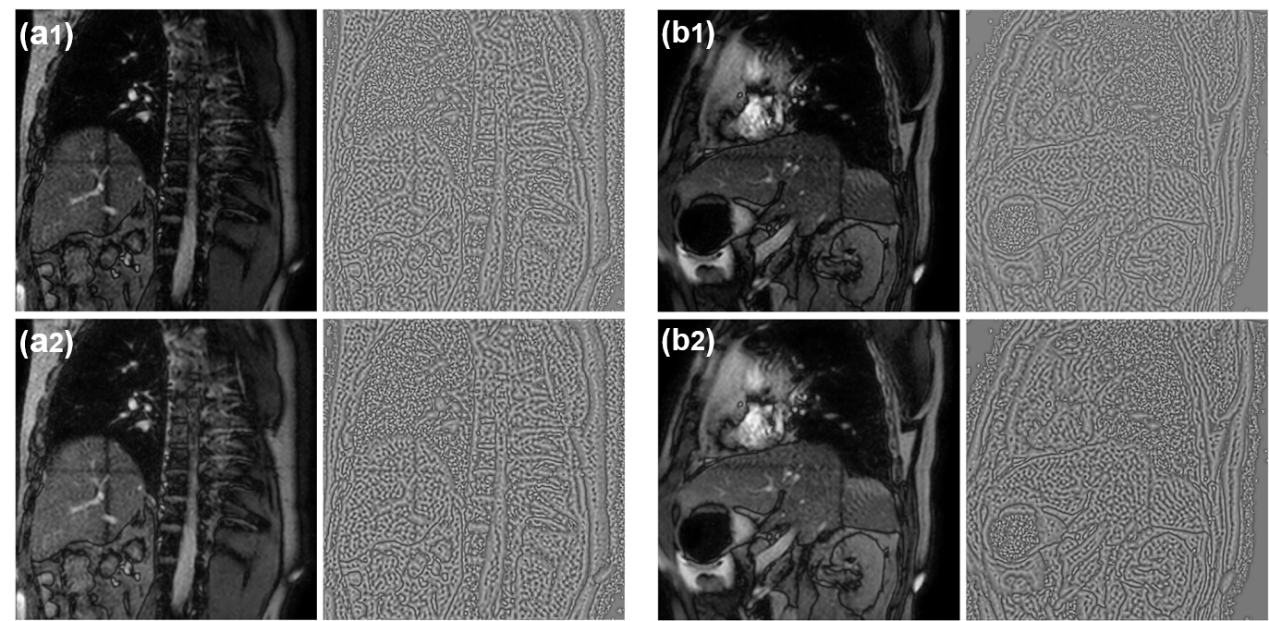

Objective:To develop a no-reference image quality assessment method using automated distortion recognition to boost MRI-guided radiotherapy precision.Methods:We analyzed 106,000 MR images from 10 patients with liver metastasis,captured with the Elekta Unity MR-LINAC.Our No-Reference Quality Assessment Model includes:1)image preprocessing to enhance visibility of key diagnostic features;2)feature extraction and directional analysis using MSCN coefficients across four directions to capture textural attributes and gradients,vital for identifying image features and potential distortions;3)integrative Quality Index(QI)calculation,which integrates features via AGGD parameter estimation and K-means clustering.The QI,based on a weighted MAD computation of directional scores,provides a comprehensive image quality measure,robust against outliers.LOO-CV assessed model generalizability and performance.Tumor tracking algorithm performance was compared with and without preprocessing to verify tracking accuracy enhancements.Results:Preprocessing significantly improved image quality,with the QI showing substantial positive changes and surpassing other metrics.After normalization,the QI's average value was 79.6 times higher than CNR,indicating improved image definition and contrast.It also showed higher sensitivity in detail recognition with average values 6.5 times and 1.7 times higher than Tenengrad gradient and entropy.The tumor tracking algorithm confirmed significant tracking accuracy improvements with preprocessed images,validating preprocessing effectiveness.Conclusions:This study introduces a novel no-reference image quality evaluation method based on automated distortion recognition,offering a new quality control tool for MRIgRT tumor tracking.It enhances clinical application accuracy and facilitates medical image quality assessment standardization, with significant clinical and research value.